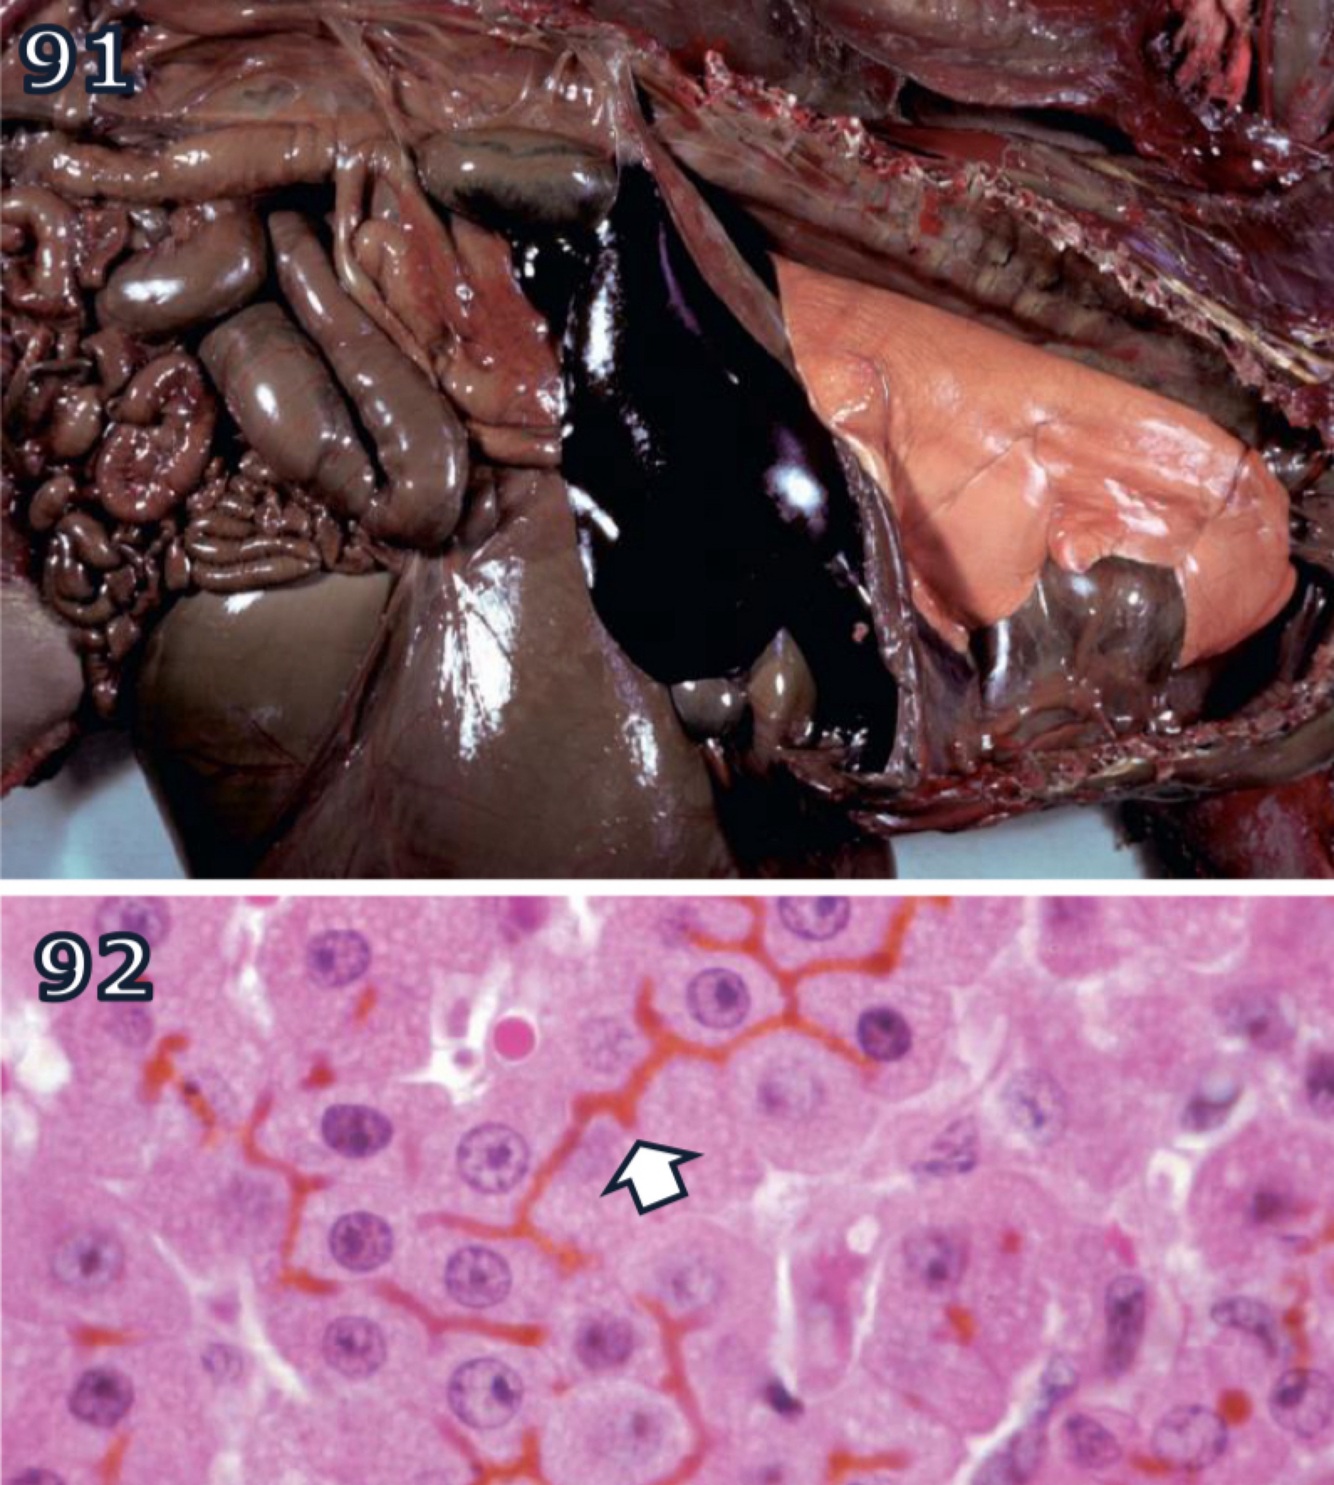

Parasitic Hematin

Hematogenous Pigments

A

prasites infecting or consuming RBCs liberate heme during proteolysis of Hgb

free heme is toxic but parasites have evolved to aggregate it into heme dimers

accounts for blacking of migration tracts by juvenile liver flukes in ruminants + for black speckling of lungs in macaques infested w/ lung mite